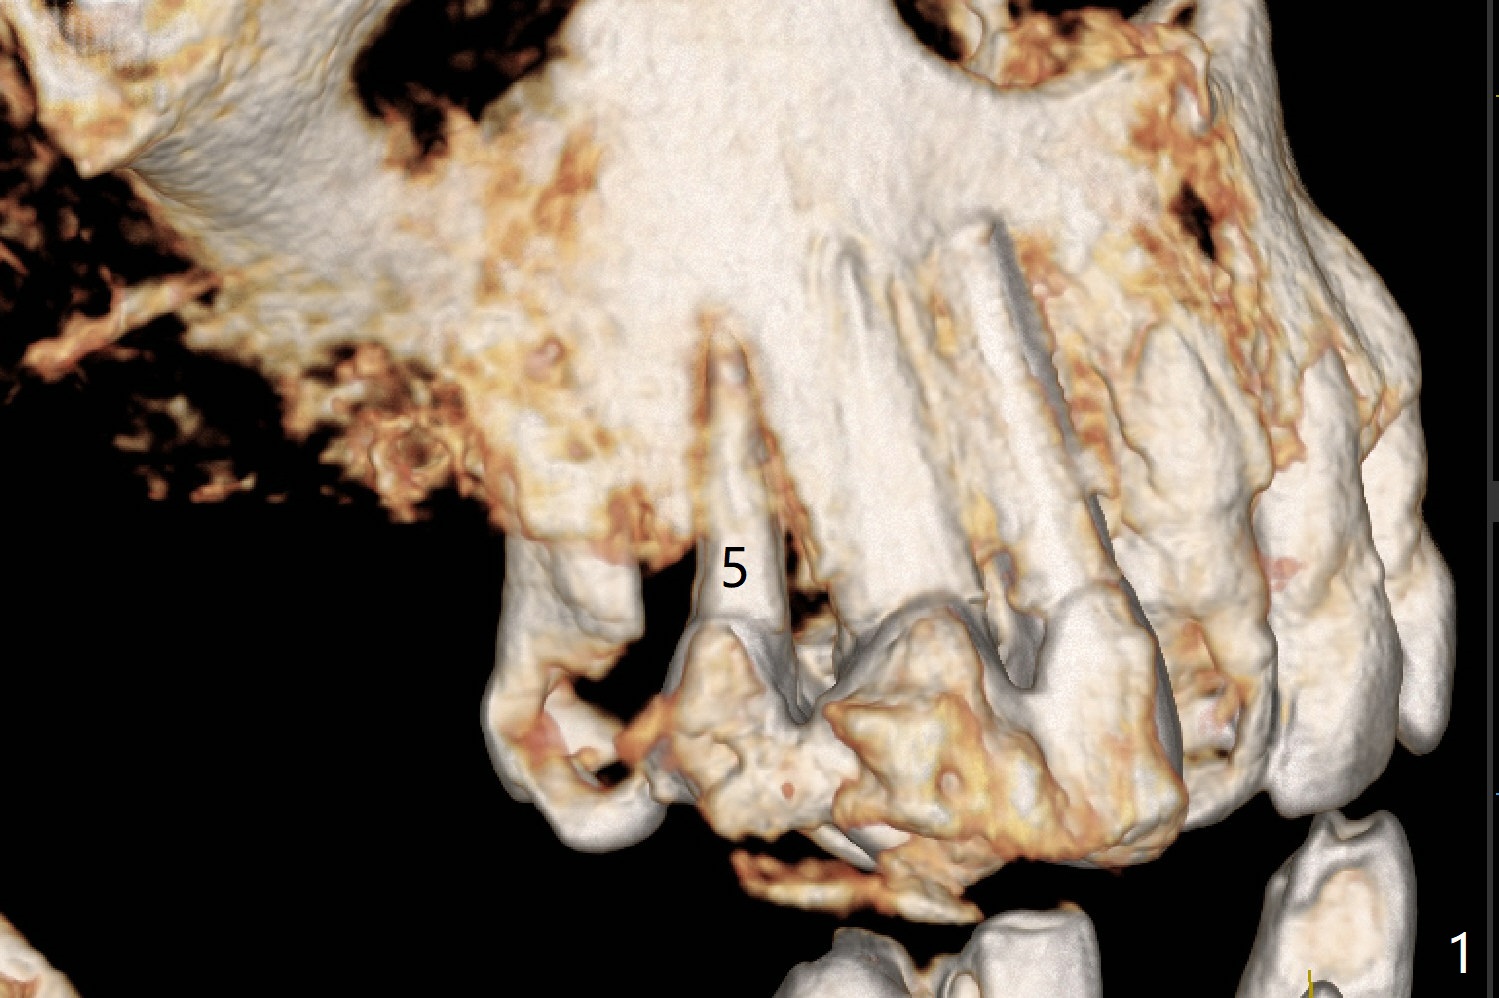

A 74-year-old woman requests treatment for a loose, tender tooth in the upper right quadrant (Fig.1). It may be due to occlusal trauma from the opposing implant tooth (Fig.2 arrow) and endo failure (Fig.2 coronal section). Because of history of low bone density and buccal placement at #7 with low primary stability, a small diameter implant will be placed palatally at #5. Either a 4x13 mm bone-level (Fig.3) or 4x17 mm tissue-level implant will be placed.